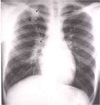

What kind of shape should the diaphragm form on a normal CXR?

* Dome-shape * Costophrenic angle (red circle)

32

True or False: Normal pleural is not visible in a healthy person's CXR.

* True * You should not be able to see the pleural in a normal CXR. * The only time you should see the pleural is when air is trapping between the chest wall or the mediastinum and lungs.